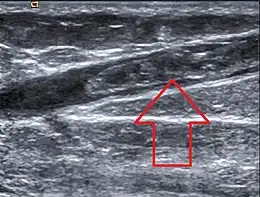

Image échographique montrant une thrombose de la grande veine saphène

Le diagnostic repose généralement sur l'échographie lorsque la veine est accessible par cet examen[1].